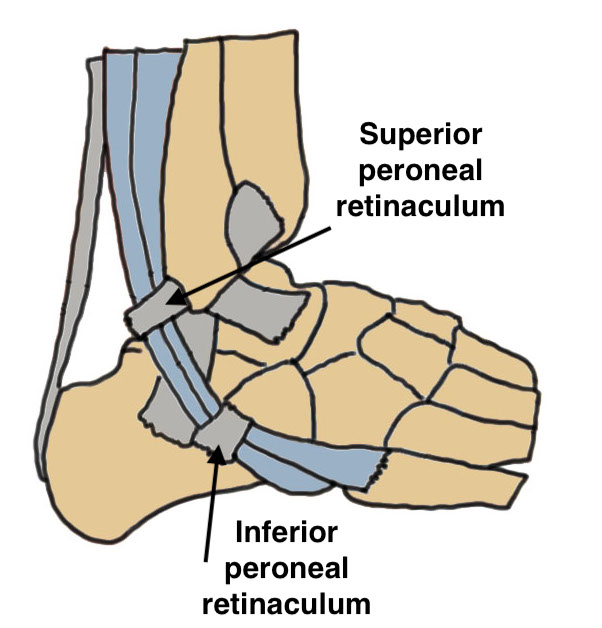

Anatomy

Peroneus longus (PL) posterolateral to Peroneus brevis (PB)

Run in fibro-osseous tunnel behind fibula

| Fibro-osseous tunnel | Superior Peroneal Retinaculum (SPR) | Inferior peroneal retinaculum |

|---|---|---|

|

Retro-malleolar groove lined by fibrocartilage |

Fibrocartilaginous ridge (FCR) - on fibula |

Lateral wall calcaneum below sinus tarsi No role in stability |

|

Fibular anterior PTFL / CFL / PITLF medial |

2 bands - fibula to lateral Tendo Achilles - fibula to posterolateral calcaneum |